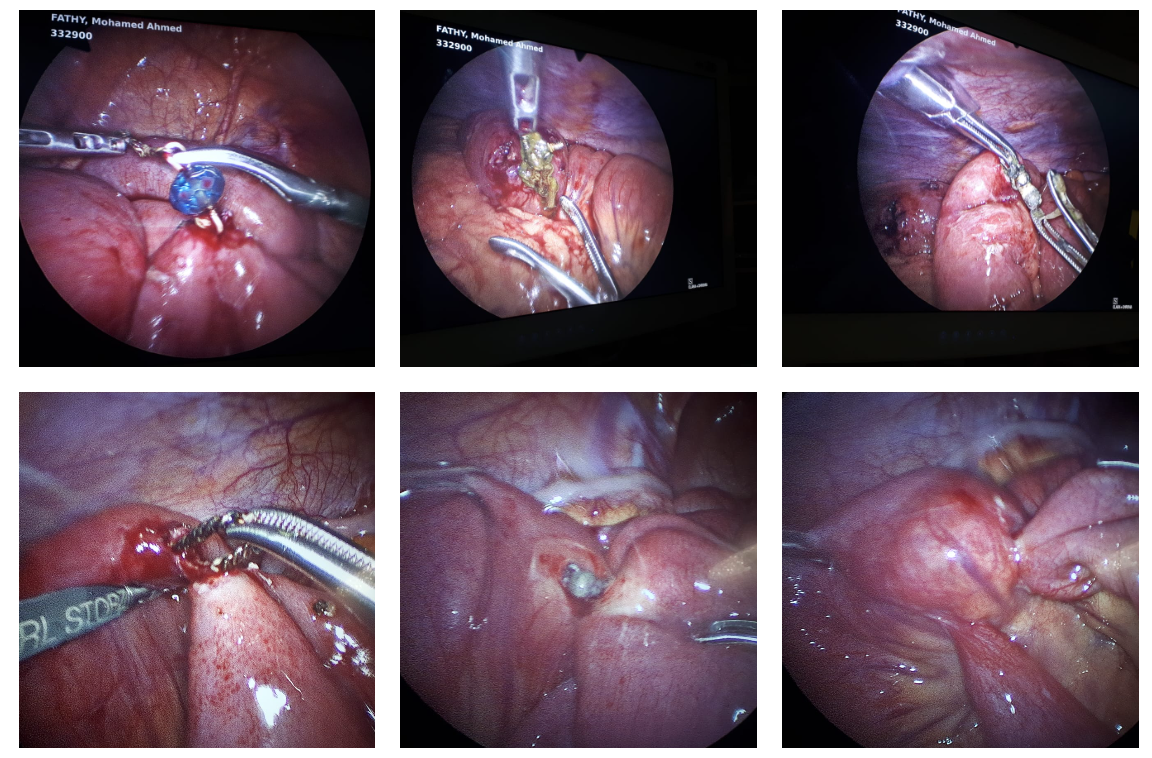

16 Pieces of Magnet and Metals Retrieved and 10 Entero-enteric Fistulae Repaired Laparoscopically

Complex laparoscopic retrieval of 16 magnetic and metallic foreign bodies with repair of 10 entero-enteric fistulae.